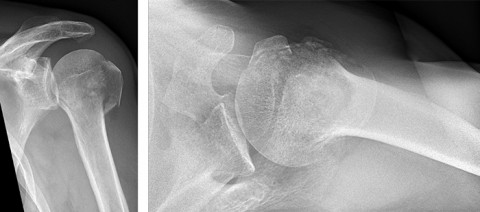

Uns lagen die auswärtigen Röntgenbilder sowie die 3 Tage später von uns durchgeführten Röntgenbilder der linken Schulter vor. Diese zeigten einen eindeutigen Bruch des Oberarmkopfes in mehrere Teile. Im Vergleich der dieser Aufnahmen waren keine Verschiebung des Bruches sichtbar. Das Röntgenbild gibt in solchen Fällen zwar einen guten Anhaltspunkt über die Verletzungsart. Um jedoch eine sichere Aussage darüber treffen zu können, ob eine Operation notwendig ist oder nicht, veranlassten wir ein Computertomogramm der linken Schulter. Mit diesem speziellen Schnittbildröntgen lassen sich die Stellungsverhältnisse der Fraktur exakt darstellen und beurteilen. Geachtet wird vor allem, ob der Bruch abgekippt oder gestaucht ist, wie viele Fragmente existieren und wie diese zueinander stehen. Die heutigen CT-Verfahren erlauben auch eine dreidimensionale Darstellung der Knochenverhältnisse.

Das CT zeigte letztendlich einen Bruch mit vier Teilfragmenten. Diese waren jedoch nicht bedeutend verschoben und es lag eine stabile Fraktursituation vor, da auch im Vergleich zur 1 Woche zurückliegenden Initialbildgebung keine weitere Verschiebung des Bruches stattfand. In Anbetracht dieser Befunde konnten wir dem Patienten klar ein nicht-operatives Vorgehen empfehlen. Wäre die Verschiebung der Fragmente nicht mehr im tolerablen Bereich gewesen bzw. wäre der Bruch zunehmend abgekippt, wäre eine chirurgische offene Bruchstabilisierung mittels Platte und Schrauben (=Plattenosteosynthese) notwendig gewesen.